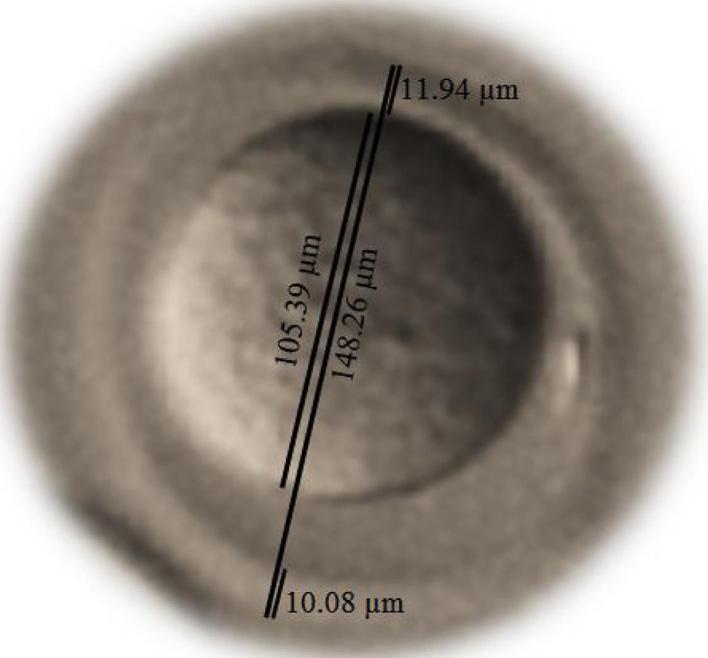

Embryo morphometry showed that the total diameter and the cytoplasm diameter of the study group embryos suffered significant reduction compared to the control group, 1 day after the last irradiation (p < 0.05), but the diameter of the perivitelline space of this group's embryos had a significant increase (p < 0.05). The qualitative results during 35 days after irradiation showed that morphologically parameters of the embryos in the study group had no significant differences from the control group.

胚胎形态测量显示,与对照组相比,在最后一次照射后1天,研究组胚胎的总直径和细胞质直径显著减小(p < 0.05),但该组胚胎的卵周隙直径显著增加(p < 0.05)。照射后35天内的定性结果表明,研究组胚胎的形态学参数与对照组无显著差异。